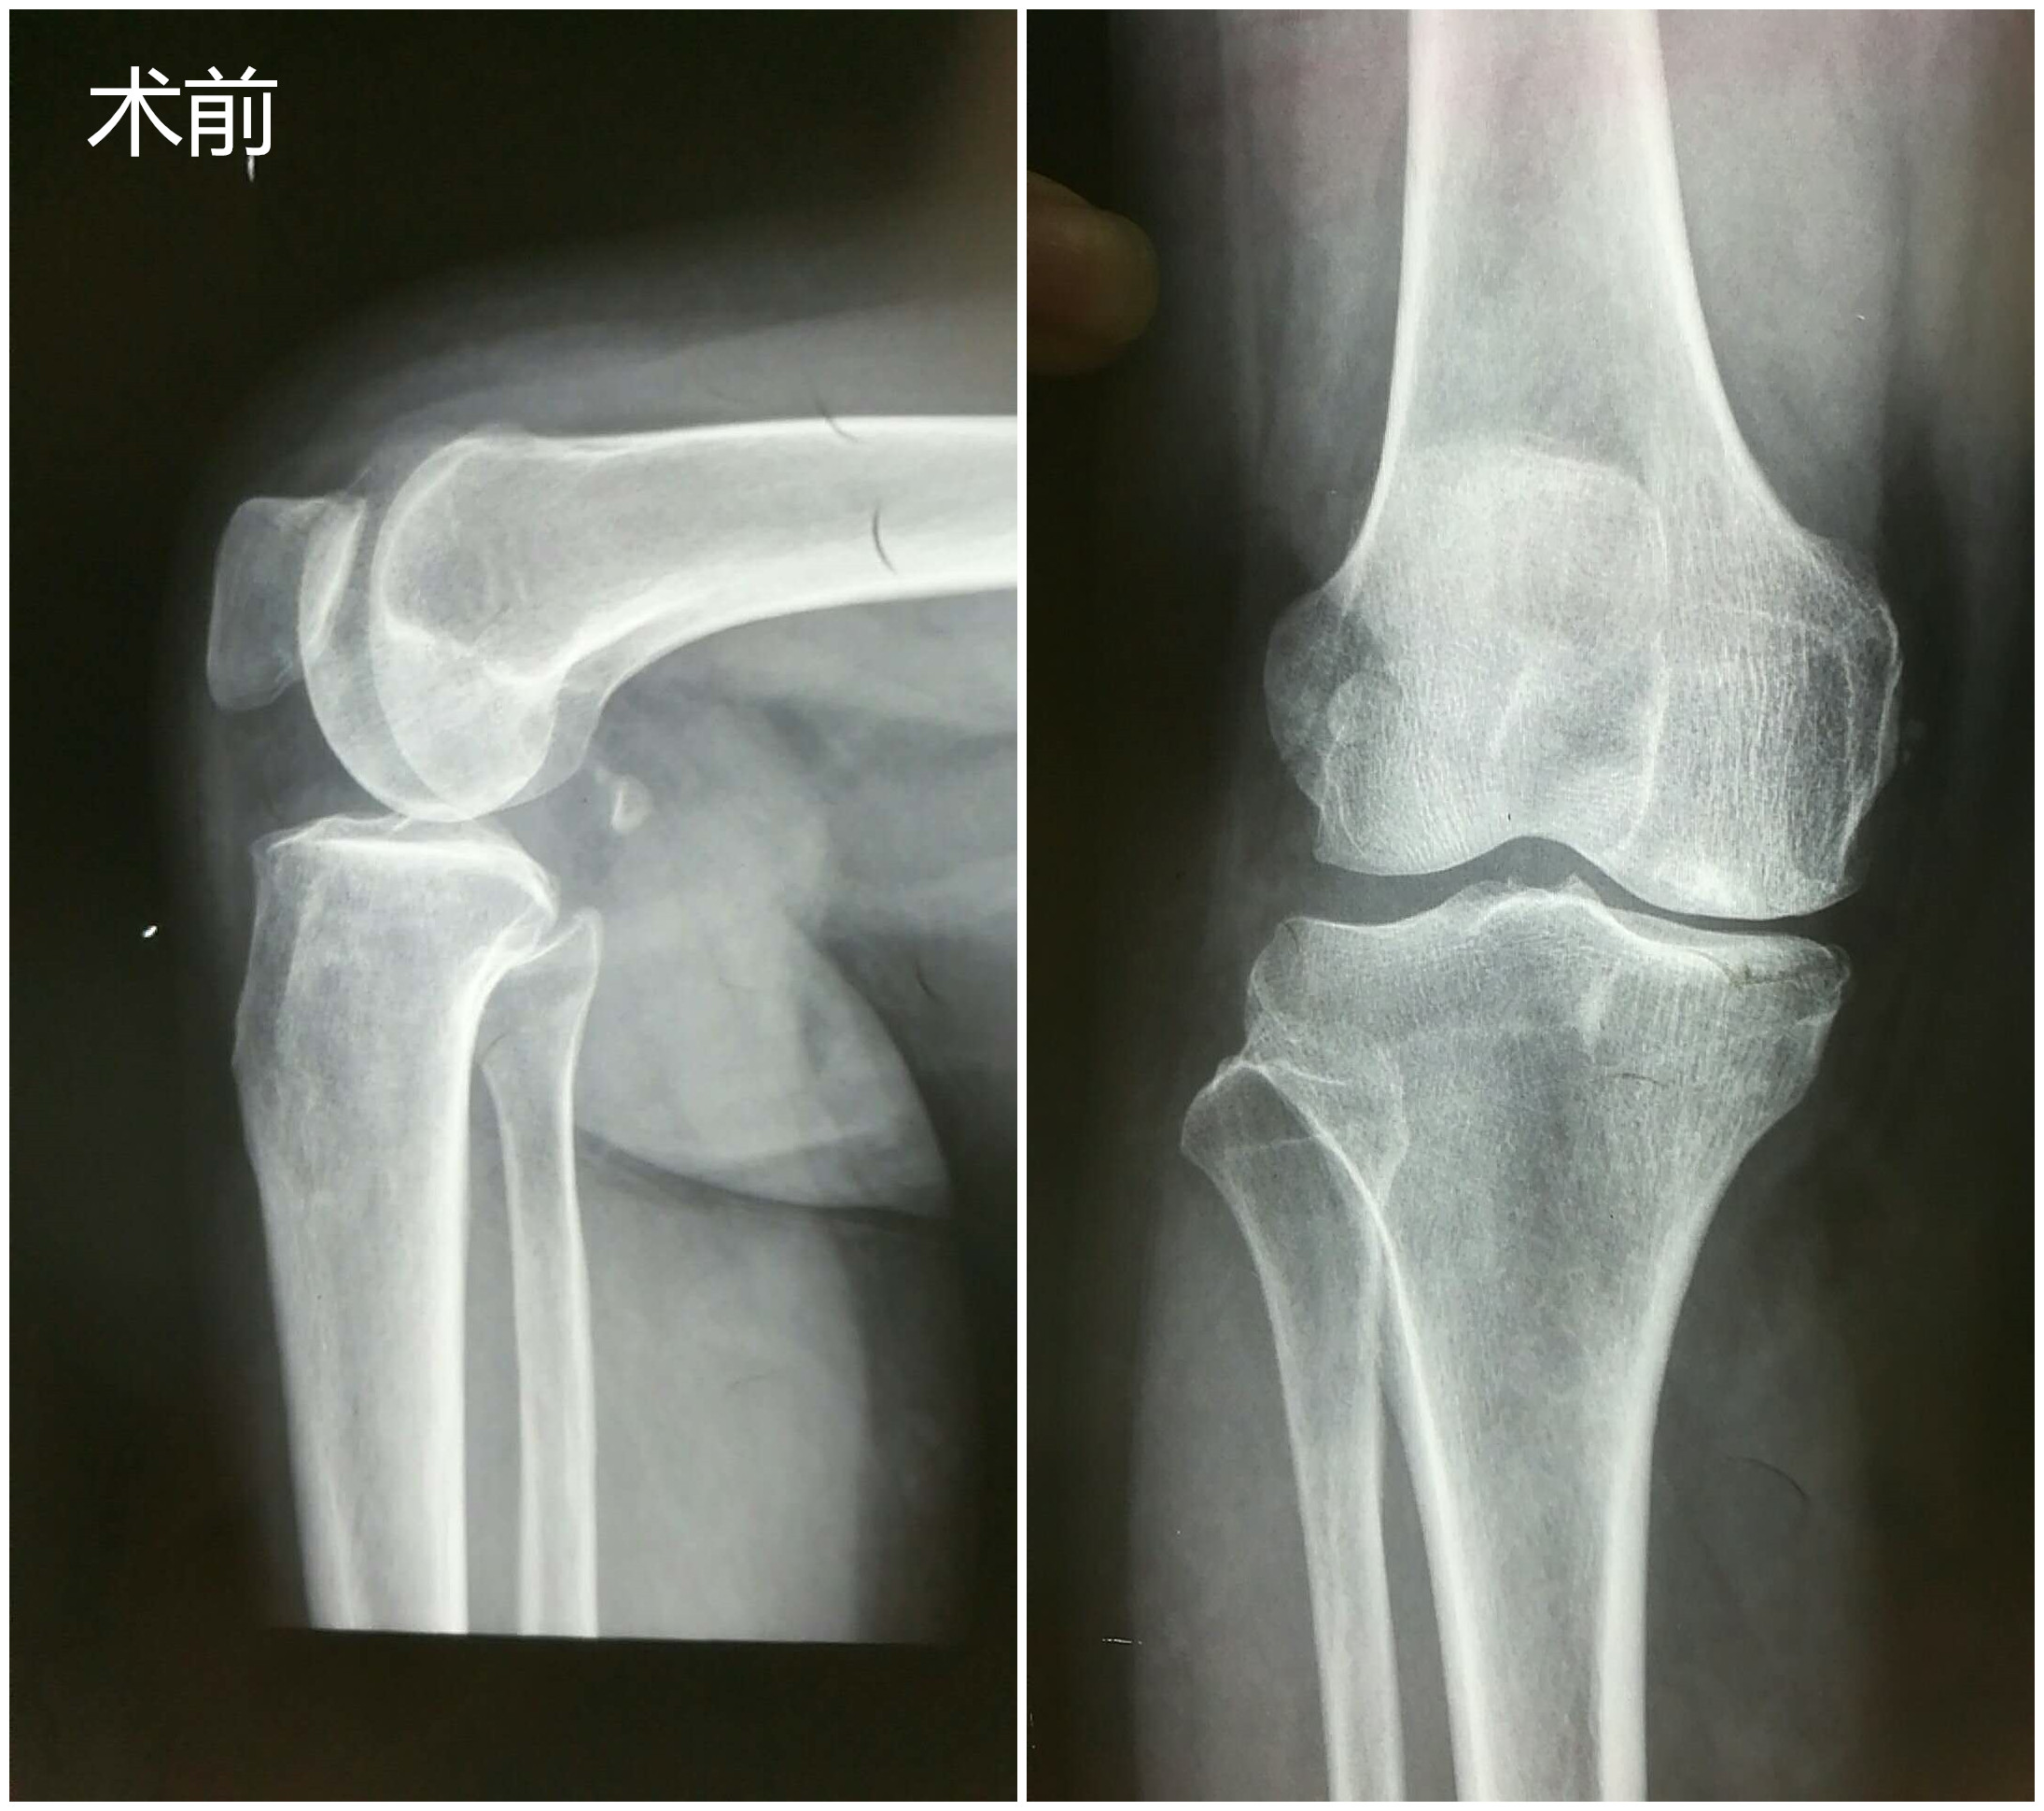

近日,我院骨一科成功完成首例右侧胫骨高位截骨术、植骨术,目前,患者病情平稳。

患者董女士,61岁,于2月前无明显诱因出现右膝关节疼痛,受凉劳累后疼痛加重,在济阳某医院行玻璃酸钠关节腔注射3次,未见明显效果,且疼痛逐渐加重。2周前,董女士自感右膝部疼痛再次加重,导致无法正常站立行走,为求进一步治疗,遂来县医院就诊,行膝关节MRI检查并收入院进一步治疗。 入院后,骨一科董孟政主任医师、张甲铠主治医师第一时间详细了解了患者病史,立即组织科室技术骨干进行病历讨论,根据患者:1.年龄较轻,只有61岁;2.仅表现为膝关节内侧疼痛,结合磁共振检查结果,考虑为单间室病变即仅膝关节内侧关节退变;3.结合下肢负重位全长片分析,其下肢负重力线內移等情况决定先不给予膝关节置换,而是采用目前更先进的胫骨高位截骨术治疗。经积极术前准备,于2017-10-21在硬膜外麻醉下实施手术,手术紧张有序进行,经过约1.5个小时,顺利完成手术。术后3天病人即能扶拐杖下床行走。目前病情恢复很快,自觉膝关节疼痛明显好转,我们将进行长期随访。

膝关节骨性关节炎是中老年常见病、多发病。关节疼痛严重者不敢负重行走,严重影响生活质量。中晚期患者保守治疗效果差,不得不接受手术治疗。以前所谓的手术治疗只有人工关节置换一种手段,但人工关节有一定的寿命,维持约15年后部分年轻患者不得不再次手术翻修,二次手术难度增加,效果也差。随着骨科技术的发展,换关节已不再是唯一、也不再是最终治疗方法。对于单间室病变(表现为单纯内侧或外侧疼痛),下肢力线不正常的中期病人,胫骨高位截骨术已成为最佳选择。胫骨高位截骨术(HTO)是通过胫骨近端截骨,把力线从磨损严重的的膝关节内侧间室转移到相对正常的外侧间室,达到改善或消除关节疼痛症状,使年轻患者推迟关节置换年龄,相当一部分甚至终生不需要再行关节置换,已成为风靡世界的膝关节骨性关节炎的治疗手段。